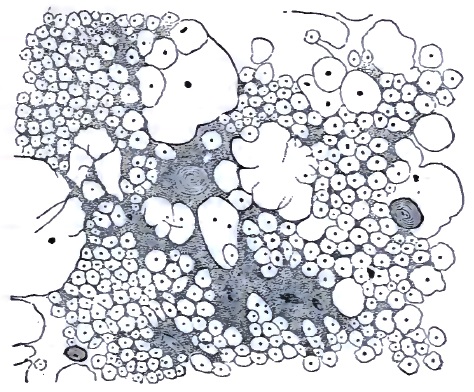

| 31. | TRANS-SECTION OF UPPER LUMBAR CORD OF A PATIENT MODERATELY ADVANCED IN TABES DORSALIS |

| 32. | CHANGES IN THE CORD IN A CASE OF DIFFUSE SPINAL SCLEROSIS |

| 33. | CHANGES IN THE CELLS OF THE ANTERIOR HORN IN DIFFUSE SPINAL SCLEROSIS (SAME CASE AS FIG. 32) |